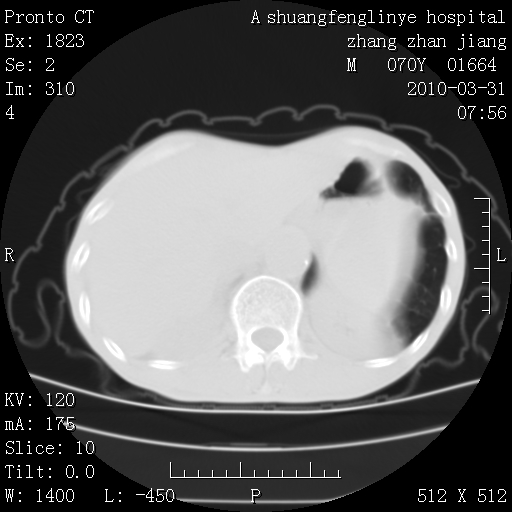

双上肺继发型tb并左上空洞形成,主动脉冠脉钙化。

1)两肺上叶继发性肺结核并左肺上叶空洞形成。2)冠状动脉及主动脉钙化。